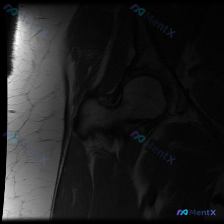

髋关节MRI提示盂唇无明显异常,但临床怀疑盂唇病变,下一步该怎么评估?

整理了一个病例讨论材料,患者临床怀疑盂唇病变,目前只提供了一张髋关节MRI T1矢状位图像。从这张图看,股骨头形态规整、髋臼结构正常、关节间隙清晰,盂唇也显示完整,但总觉得单一序列评估盂唇有局限性。大家怎么看这个病例?下一步该重点做哪些评估?